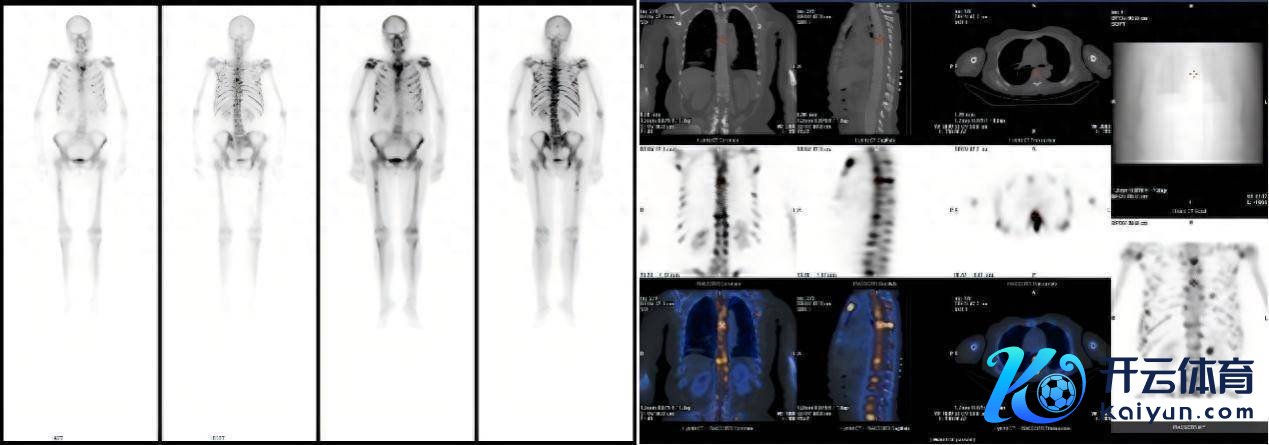

患者因不解原因发烧、剧烈骨痛伴体重骤降前来就诊。住院后,全腹及胸部CT未见赫然荒谬,但血惯例教唆白细胞、淋巴细胞、血小板及红细胞计数均显耀镌汰。为进一步探明病因,临床医师安排了全身骨扫描(SPECT/CT),效果表露全身多处骨骼辐射性浓聚,初步怀疑为肿瘤骨转化,其诊疗标的指向实体肿瘤,但其CT却未见赫然病灶,会诊堕入了窘境。临床医师连忙安排不错全身扫描尤其对肿瘤病变尤为敏锐的PET-CT搜检。

△患者全身骨扫描(SPECT/CT)核医学显像图